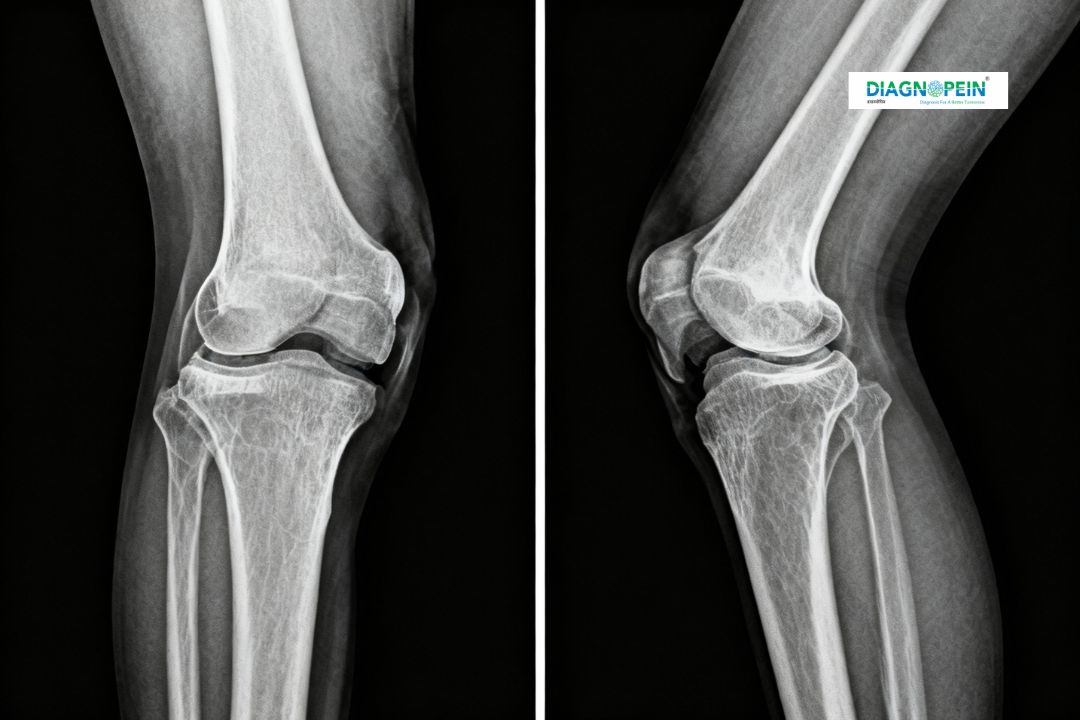

The X-Ray Both Knee Standing AP/Lat View is a specialized diagnostic imaging test that captures clear frontal (AP – Anteroposterior) and lateral (side) views of both knees while the patient is standing. This position helps in assessing the natural alignment of the knees under body weight, giving doctors a realistic picture of how the joint functions during daily activities.

Standing knee X-rays are vital for evaluating joint alignment, detecting degenerative changes, and planning orthopedic treatments. When both knees are examined together in standing position, it allows the doctor to compare the load distribution between knees and determine if there is joint space loss due to osteoarthritis or ligament wear.

2. In the AP (Anteroposterior) view, the X-ray beam passes from front to back of the knees.

3. In the Lateral view, imaging is taken from the side to evaluate joint spacing and bone structure.

1. Joint space width

2. Bone alignment and positioning

3. Cartilage degeneration

4. Signs of osteoarthritis or injury

5. Patellar tracking and posture